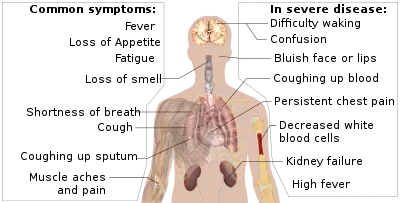

Signs and symptoms

Symptoms of COVID-19 are variable, ranging from mild symptoms to severe illness.[96][97] Common symptoms include headache, loss of smell and taste, nasal congestion and runny nose, cough, muscle pain, sore throat, fever, diarrhoea, and breathing difficulties.[96] People with the same infection may have different symptoms, and their symptoms may change over time. Three common clusters of symptoms have been identified: one respiratory symptom cluster with cough, sputum, shortness of breath, and fever; a musculoskeletal symptom cluster with muscle and joint pain, headache, and fatigue; a cluster of digestive symptoms with abdominal pain, vomiting, and diarrhoea.[98] In people without prior ear, nose, and throat disorders, loss of taste combined with loss of smell is associated with COVID-19 and is reported in as many as 88% of cases.[99][100][101]

Prognosis

The severity of COVID-19 varies. It may take a mild course with few or no symptoms, resembling other common upper respiratory diseases such as the common cold. In 3–4% of cases (7.4% for those over age 65) symptoms are severe enough to cause hospitalization.[148] Mild cases typically recover within two weeks, while those with severe or critical diseases may take three to six weeks to recover. Among those who have died, the time from symptom onset to death has ranged from two to eight weeks. Prolonged prothrombin time and elevated C-reactive protein levels on admission to the hospital are associated with severe course of COVID-19 and with a transfer to intensive care units (ICU).[149][150]

Between 5% and 50% of COVID-19 patients experience long COVID,[151] a condition characterized by long-term consequences persisting after the typical convalescence period of the disease.[152][153] The most commonly reported clinical presentations are fatigue and memory problems, as well as malaise, headaches, shortness of breath, loss of smell, muscle weakness, low fever and cognitive dysfunction.[154][155][156][157]